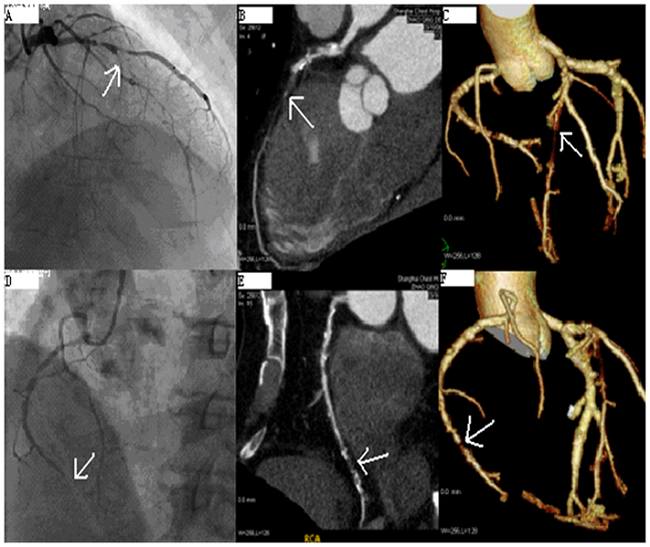

Coronary Computed Tomography Angiography (CCTA) merupakan tindakan medis pencitraan noninvasif untuk mendeteksi sumbatan arteri koroner yang dapat menyebabkan sindrom koroner akut atau infark miokard akut. [1,2]

CCTA merupakan pencitraan yang memiliki fungsi untuk melihat keadaan arteri koroner. Berbeda dengan angiografi koroner yang perlu memasukkan kateter ke dalam arteri koroner, CCTA bersifat noninvasif dan memiliki tingkat akurasi yang tinggi. [1,4]

Penggunaan CCTA sudah banyak digunakan dalam menentukan keadaan arteri koroner jantung pada pasien nyeri dada akut. Studi Miller JM et al menunjukkan bahwa CCTA memiliki sensitivitas 85% dan spesifisitas 90% dalam mendeteksi stenosis arteri koroner lebih dari 50%. [5,6]

Beberapa studi juga sudah menunjukkan bahwa CCTA efektif dalam mengeksklusi stenosis arteri koroner pada pasien. Hal ini dibuktikan pada sebuah studi yang menemukan bahwa CCTA memiliki negative predictive value (NPV) yang tinggi, yaitu sebesar 83% pada diagnosis stenosis arteri koroner. CCTA juga digunakan untuk mendeteksi anomalitas koroner, mengevaluasi stenosis atau oklusi coronary artery bypass grafting (CABG), dan mengevaluasi sten arteri koroner. [6-9]